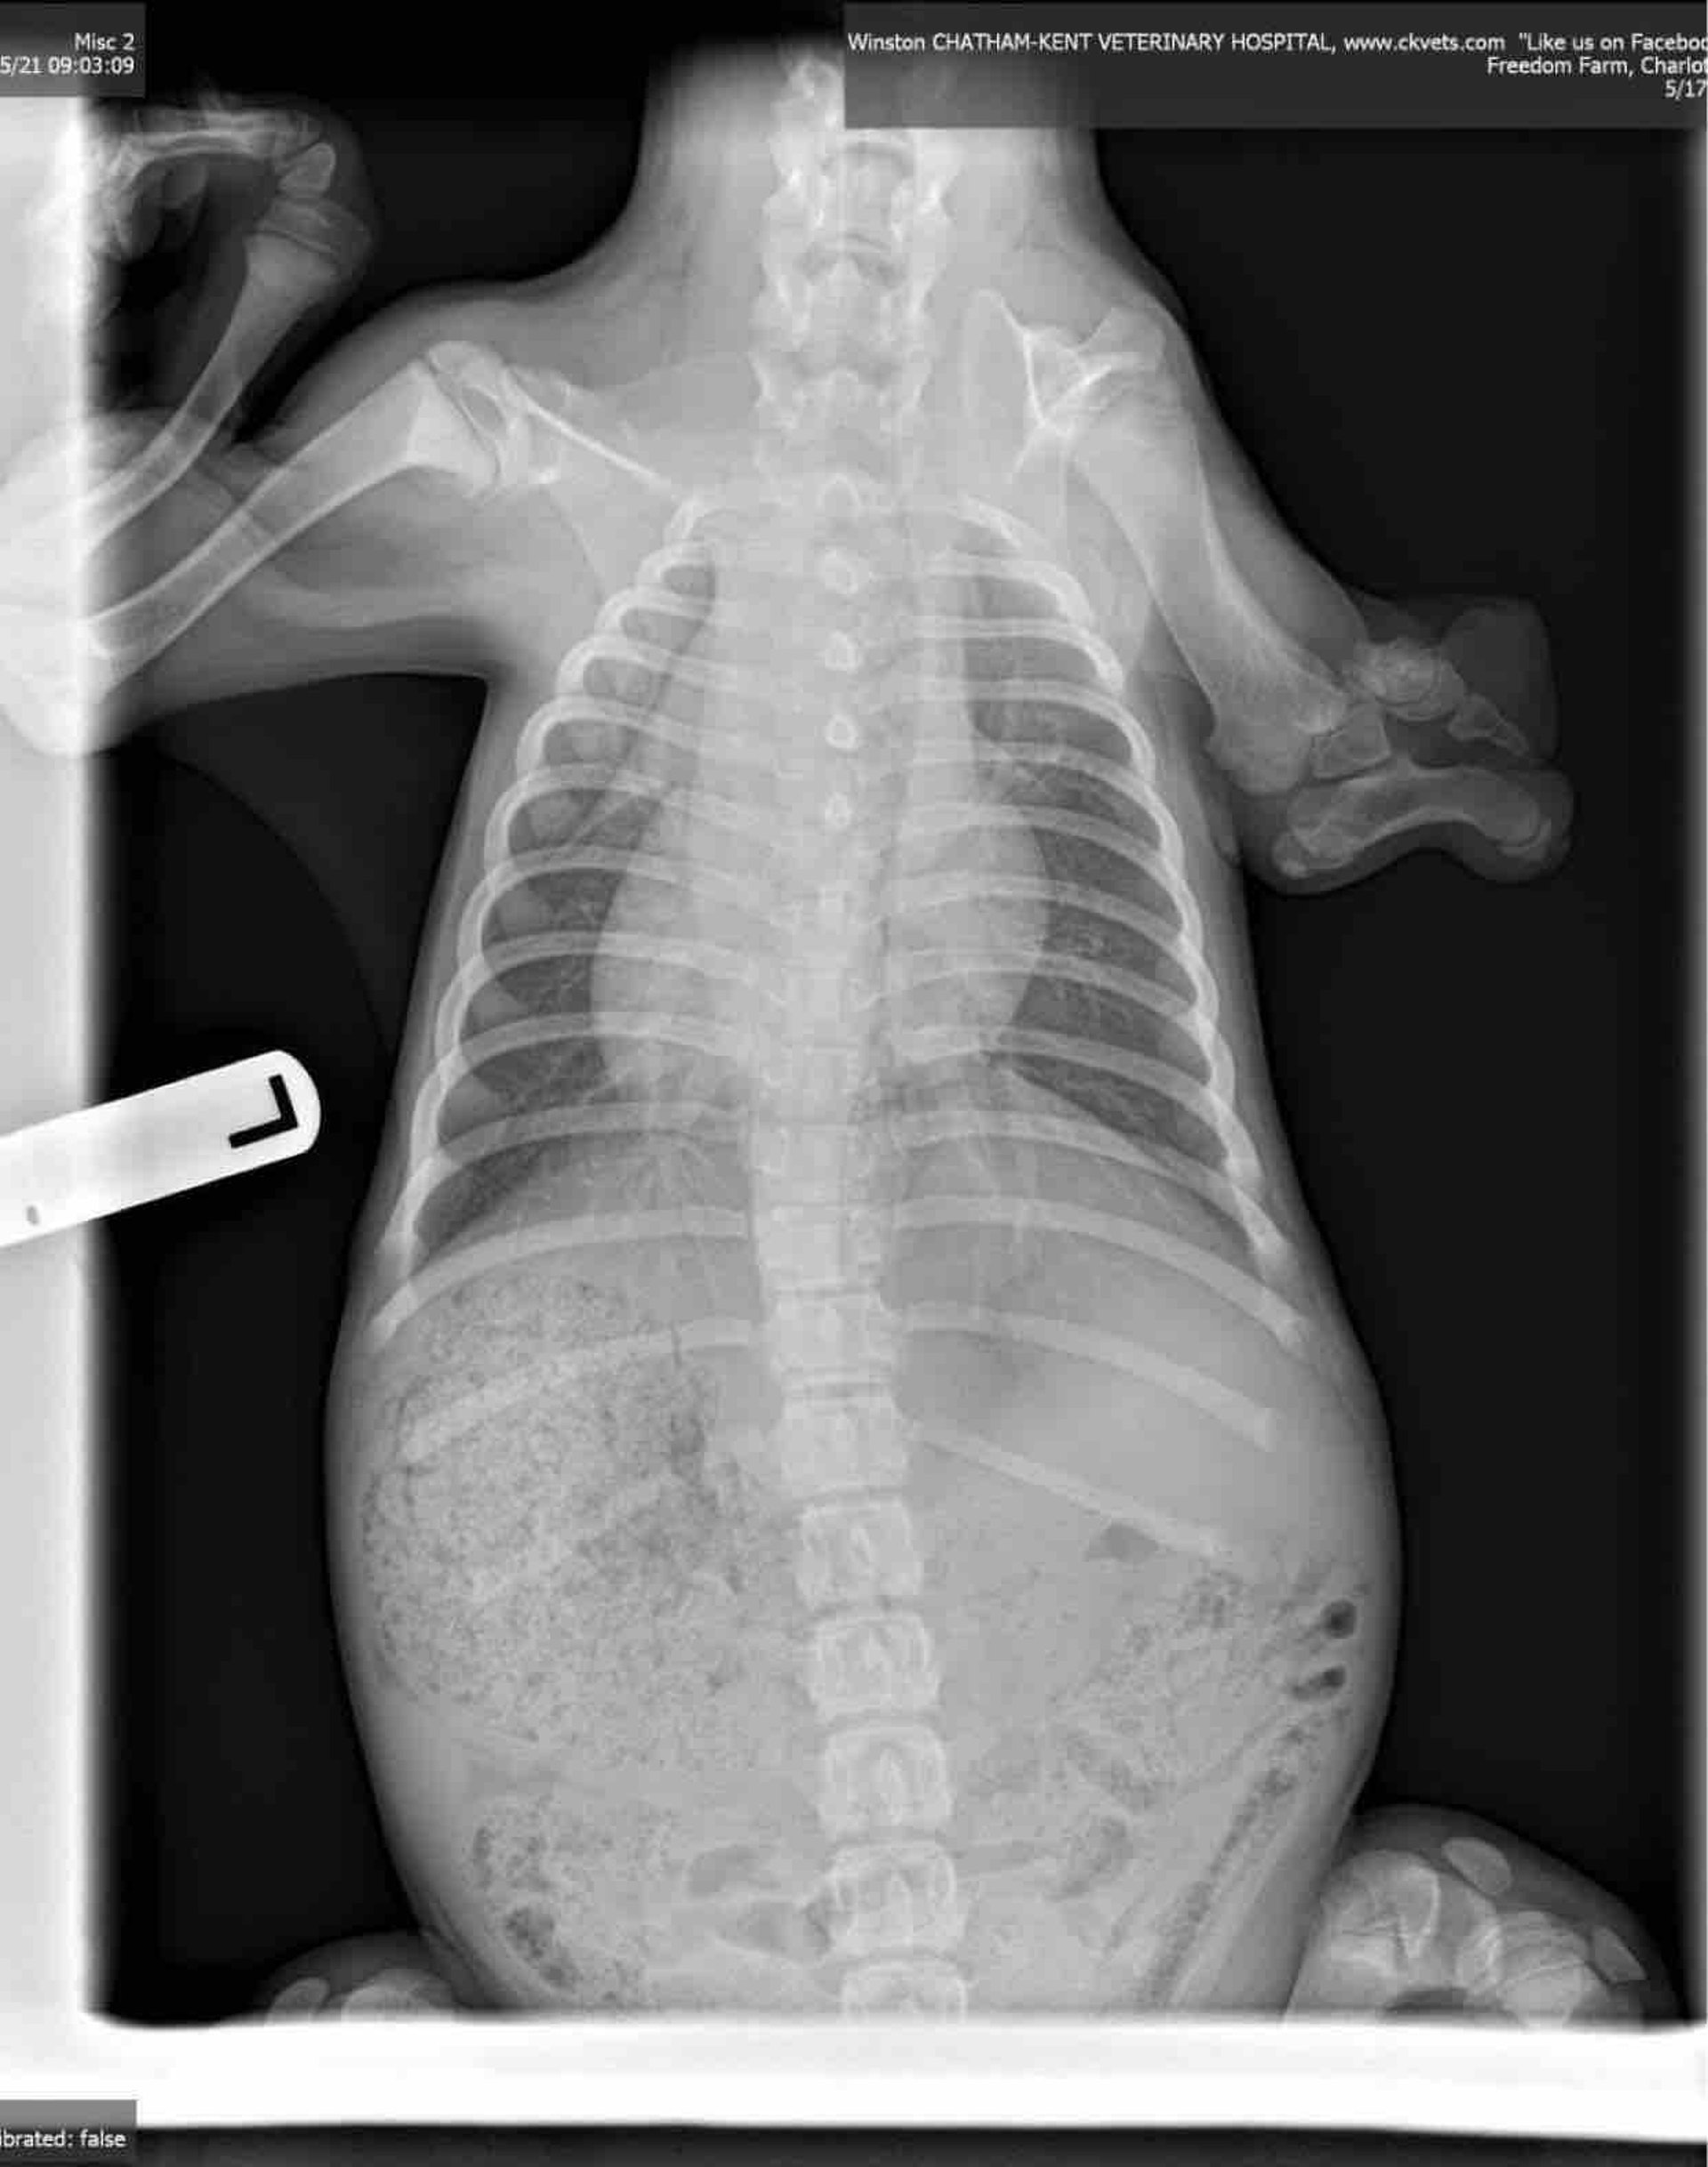

Edwards帶小狗Winnie去看獸醫,在X光顯示下,牠連前胸的肋骨也沒有,因此生命非常脆弱,Edwards更為小狗募資,希望藉着善款讓牠接受更好的治療。雖然沒法令Winnie長出前肢,但牠天性樂觀而且常常面帶笑容,令農場裏加添了不少快樂氣氛!